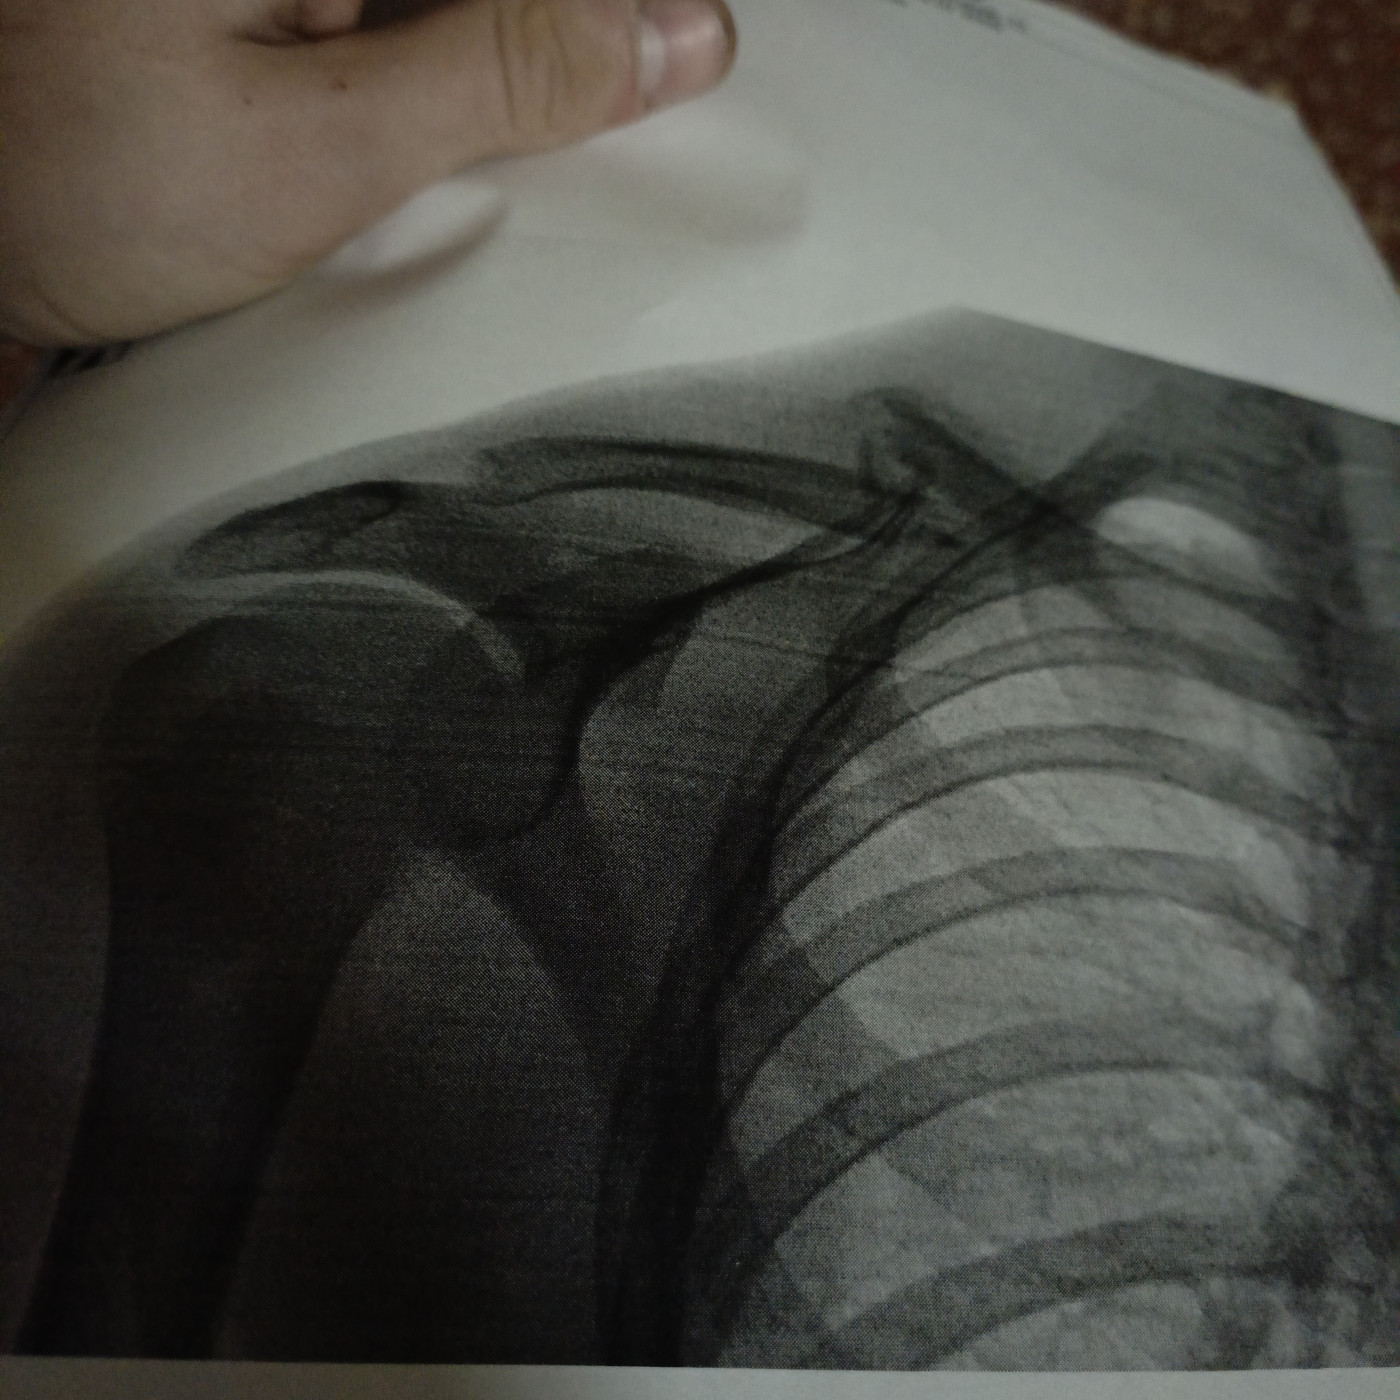

Перелом ключицы со смещениемСломал ключицу 1.5 месяца назад упав с велосипеда. Мне поставили спицу . и сейчас выпирает головка ключицы. Что это может быть. И пройдёт ли это когда снимут спицу |

Здравствуйте. Нужно видеть снимки. ВОзможно, это костная мозоль. Выраженность может стать меньше со временем. Посетите ортопеда очно. |